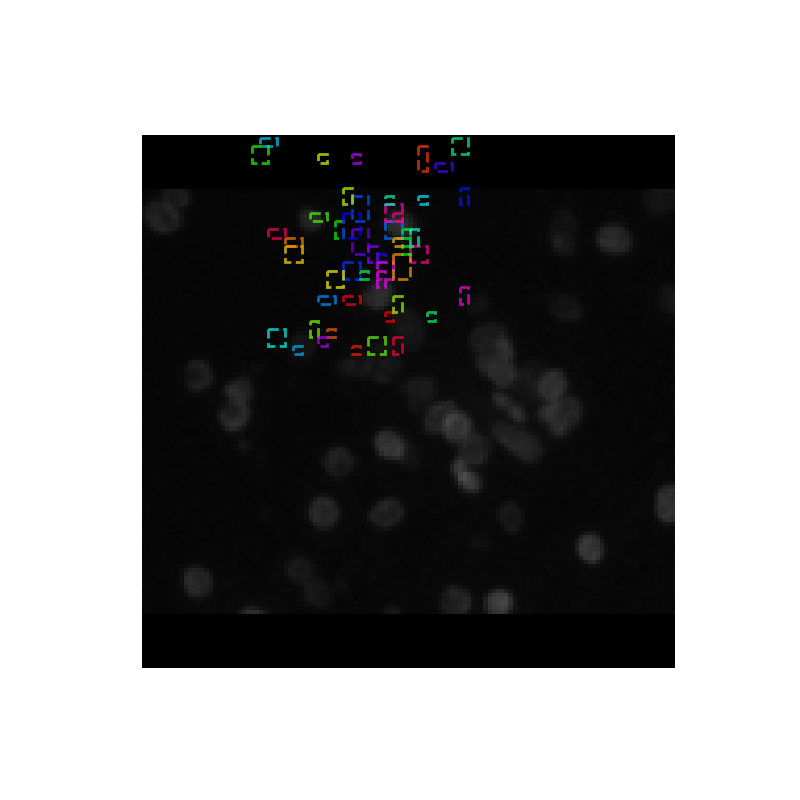

Our tool takes images of a collection of cells under different conditions as input and produces an image with bounding boxes and masks highlighting individual nucleus as output.

We finally used Mask Regional Convolutional Neural Network to come up with candidate region proposals and train the network to select the most probable regions in the image that contain a nucleus.

- Noisy data